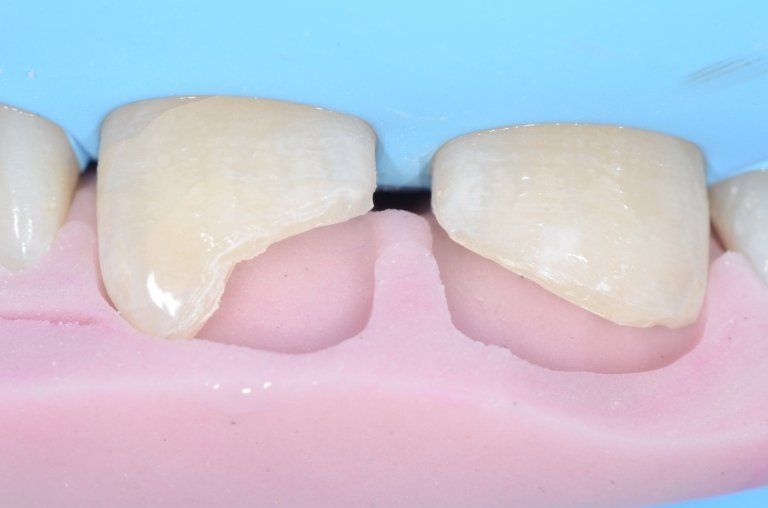

I denti da latte traumatizzati più spesso vanno incontro a necrosi con conseguente cambiamento di colore, divenendo grigiastri, segno della morte delle cellule della polpa dentaria. In altre occasioni, il dente può fratturarsi in maniera più o meno ampia: se il frammento viene ritrovato, potrà essere re-incollato in maniera invisibile, oppure verrà ricostruito con i materiali compositi.